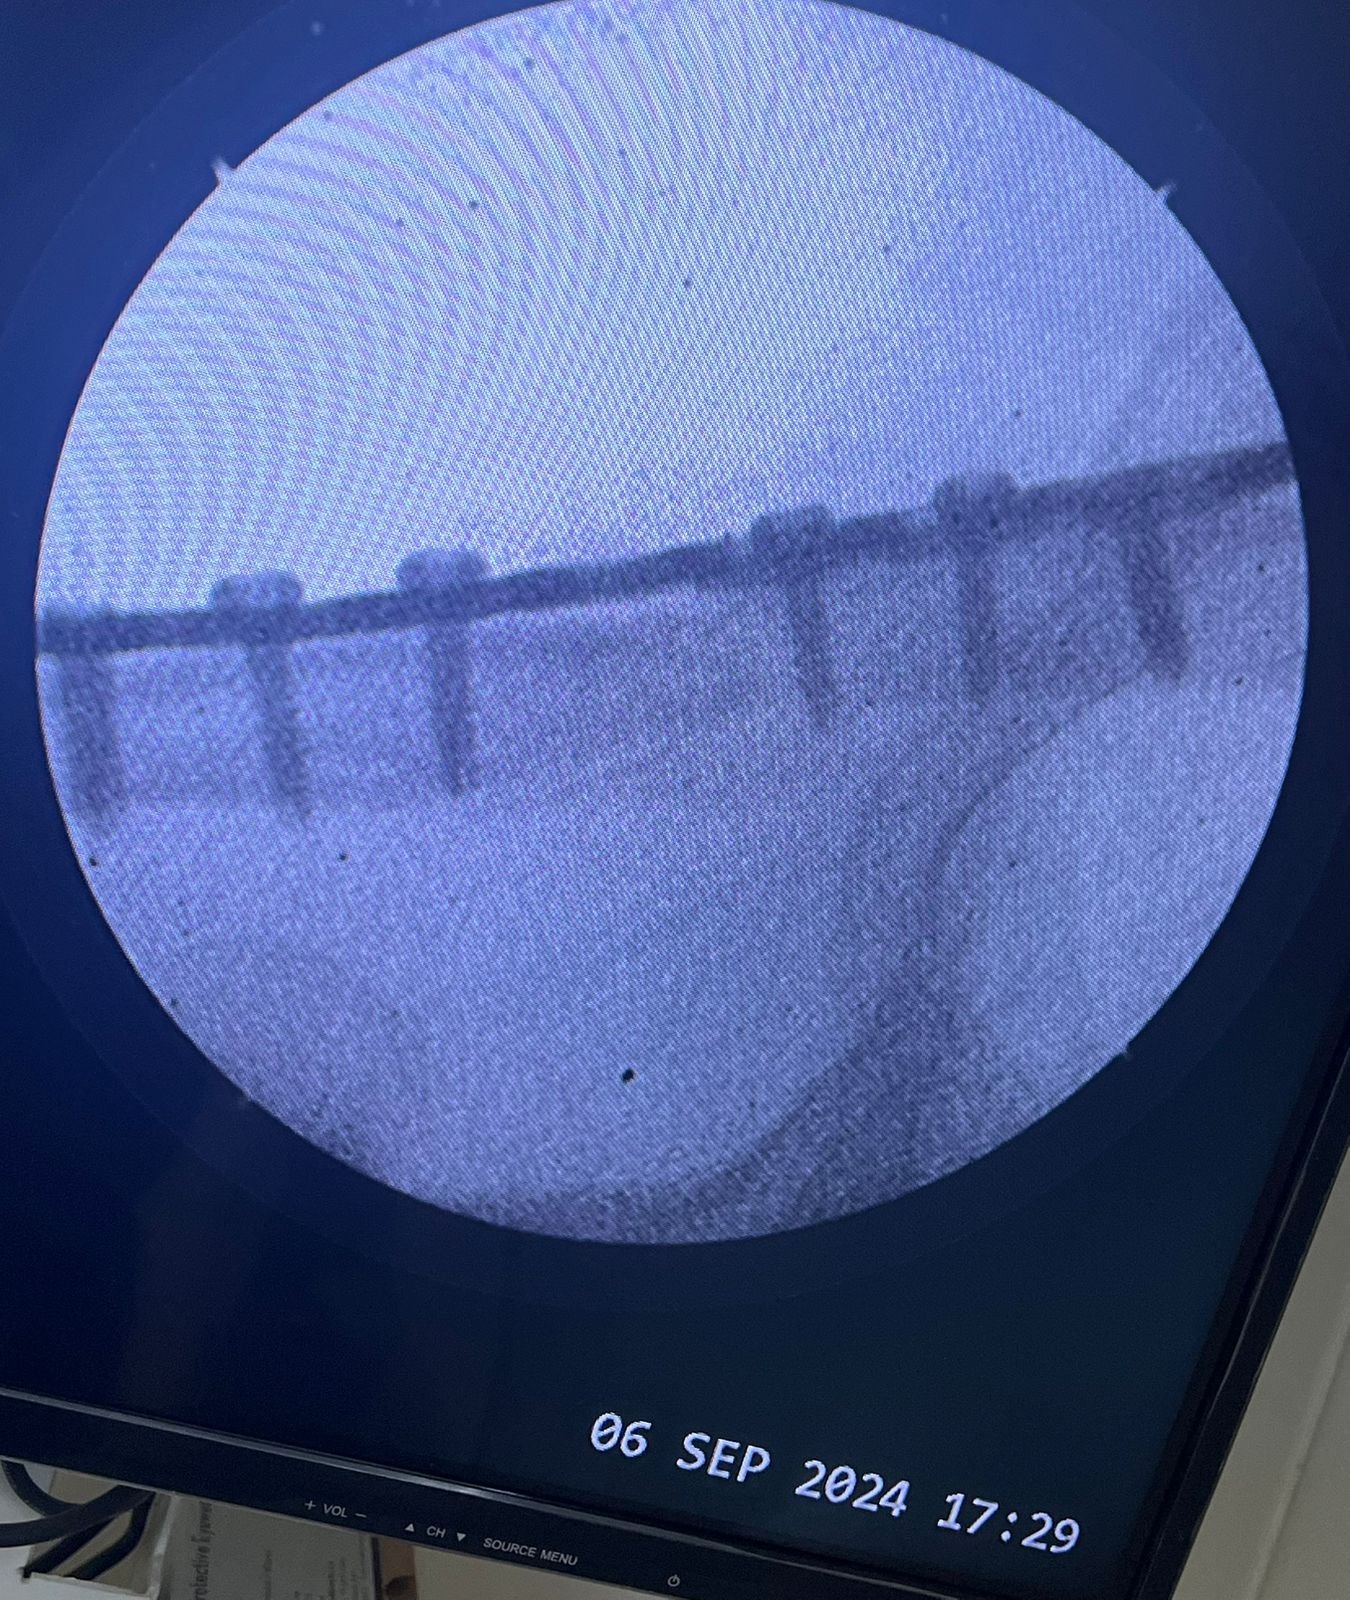

Heal fracture pre & postop | Clavicle fracture pre &

postop | Congenital foot deformity pre & post